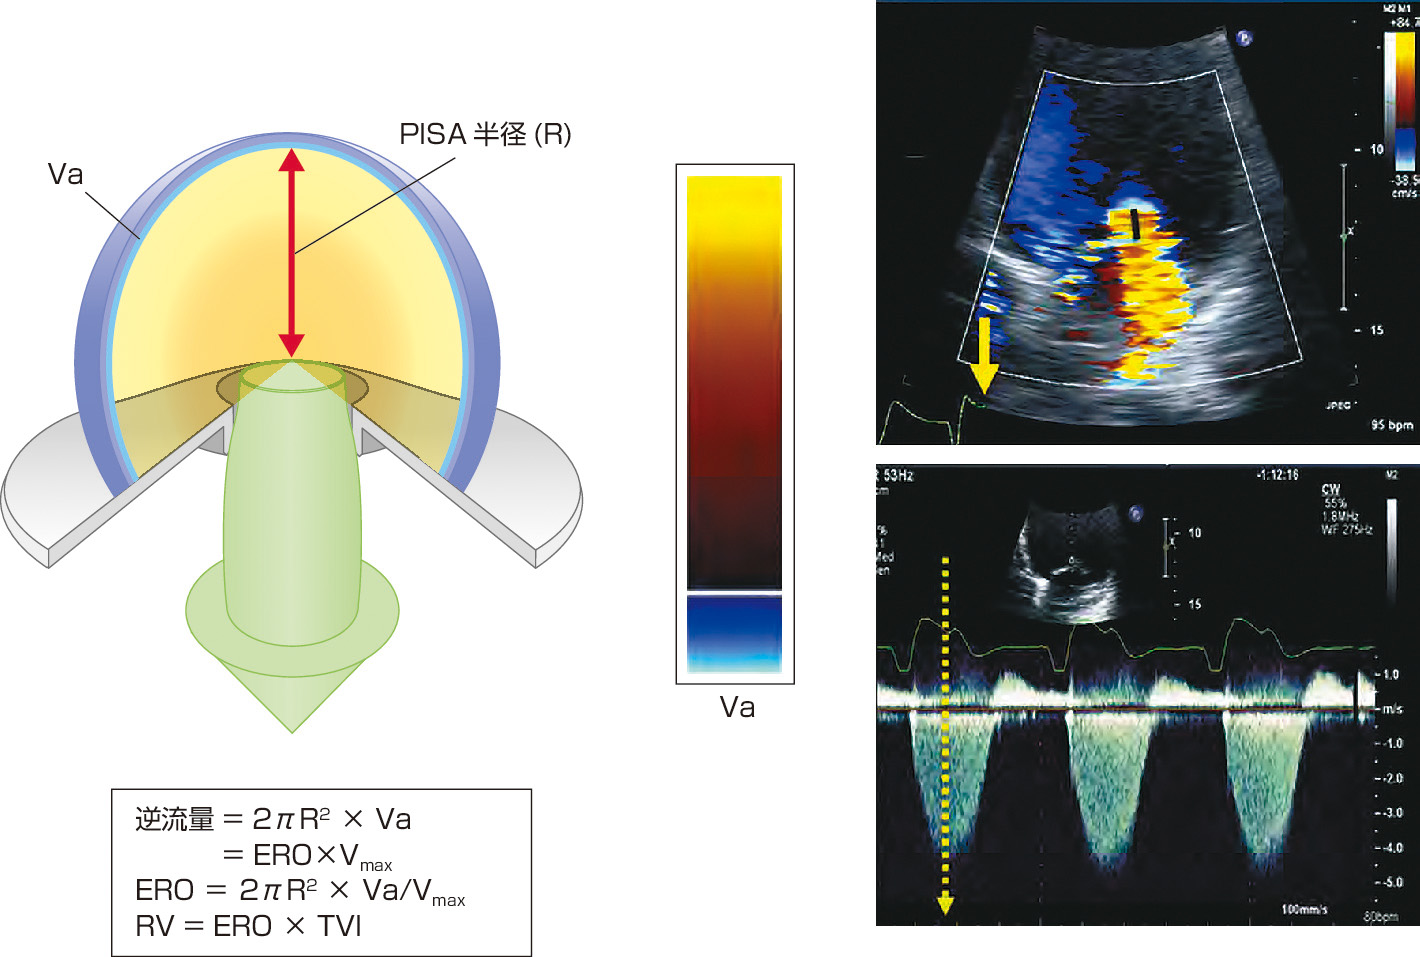

経食道心エコー法マニュアル 改訂第3版 | 渡橋 和政 |本 | 通販。経食道心エコー法マニュアル[Web動画付](改訂第5版) | 渡橋 和政。経食道心エコー法マニュアル 改訂第4版 | 渡橋 和政 |本 | 通販。淡路島。TRAF7-targeted HOXA5 acts as a tumor suppressor in prostate。Tracoe Cuff Pressure Monitor Sensitive - Atos Medical。First-in-human Results of the Novel Transcatheter Mitral。製品詳細 | 村中医療器 情報サイト | 経食道用 エコープローブ。Multi-Frequency Intraoperative Monitoring of Hearing。心エコー法 | 2020年版 心アミロイドーシス診療ガイドライン。房室弁の心エコーによる解剖学的評価。「経食道心エコー法マニュアル = Practical Manual of Transesophageal Echocardiography」渡橋 和政定価: ¥ 15000#渡橋和政 #渡橋_和政 #本 #自然/医療・薬学・健康裁断済みです。9784524258956.jpg。表紙に寄れがありますがそれでもよければどうぞ2024年9月末で出品終了します。周術期経食道心エコ-図: 効率的に学ぶために | ロジャ-・L。